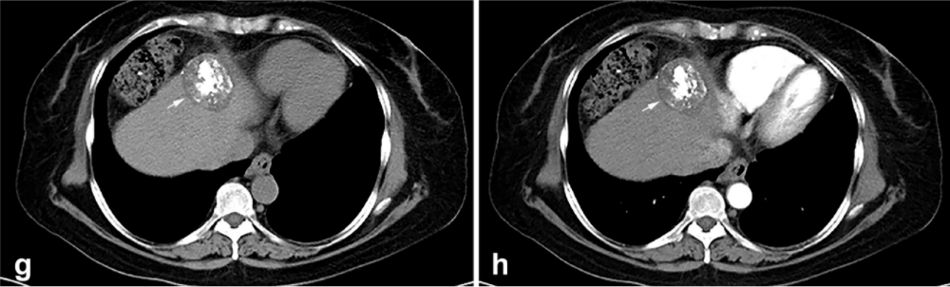

背景:由于一些原因,位于膈肌附近的腫瘤的熱消融在技術(shù)上具有挑戰(zhàn)性。首先,術(shù)中計算機(jī)掃描和超聲檢查無法清晰顯示射頻消融/微波消融切緣。第二,消融過程中不利的針分布和過熱可能導(dǎo)致肝包膜破裂,并對膈、肺和心臟造成嚴(yán)重?fù)p傷。第三,即使使用人工腹水,仍有9~22%的患者因肝周粘連或腫瘤位置靠近肝表面而導(dǎo)致膈肌熱損傷。冷凍消融可能是毗鄰膈肌的HCC的一種有前途的治療方法,因為在消融過程中使用CT和US可以很好地顯示腫瘤邊緣。盡管一些研究評估了在高危區(qū)域使用冷凍消融治療HCC,但很少有研究針對膈肌臨近區(qū)域。

① 術(shù)后 1 月腫瘤治療反應(yīng):冷凍消融術(shù)后一個月腫瘤疾病控制率達(dá)95.9%。

③ 總生存曲線和局部腫瘤進(jìn)展曲線:冷凍消融后中位生存時間為 27.3 個月,中位局部腫瘤進(jìn)展時間為 20.9 個月。